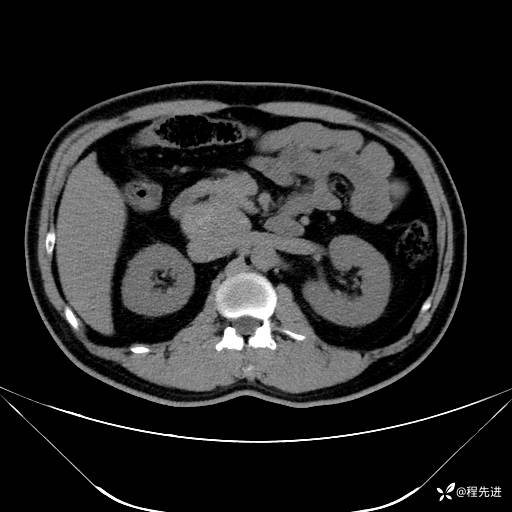

【腹盆】特别精彩病例|发现腹膜后肿物1月余

主诉:发现腹膜后肿物1月余

现病史:患者1月余前查体,行超声检查提示:后腹膜囊实性肿块;慢性胆囊炎伴胆囊内结石;无腹痛腹胀,不伴腹泻发热等;偶感腰背部酸痛。

CT平扫+增强: